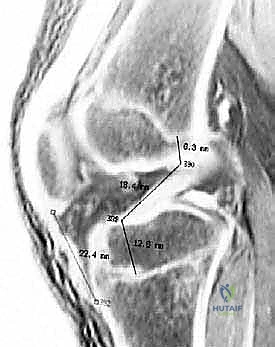

شكل 1: صورة رنين مغناطيسي سهمي تُظهر نمط الكدمة العظمية المميزة لإصابة الرباط الصليبي الأمامي الحادة (سهم رفيع). لاحظ زيادة الإشارة على الجانب الخلفي من الهضبة الظنبوبية الجانبية والجانب البعيد من عظم الفخذ عند الثلمة النهائية.

شكل 2: صورة رنين مغناطيسي سهمي عبر الجانب الجانبي للركبة، تُظهر نمط الكدمة العظمية المميزة لإصابة الرباط الصليبي الأمامي الحادة (سهم رفيع). هذه الكدمات تعكس الصدمة التي تحدث عندما يندفع عظم الساق إلى الأمام على عظم الفخذ.